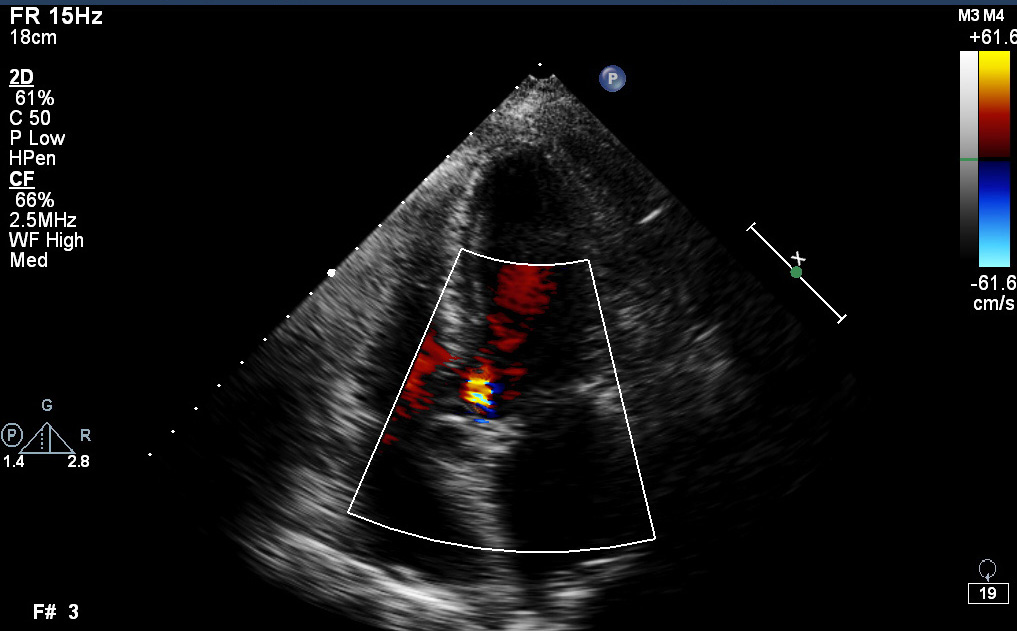

Preoperative echocardiography demonstrated a dilated sinutubular junction (STJ), preserved sinus dimensions and moderate to severe aortic valve insufficiency with central regurgitant jet.